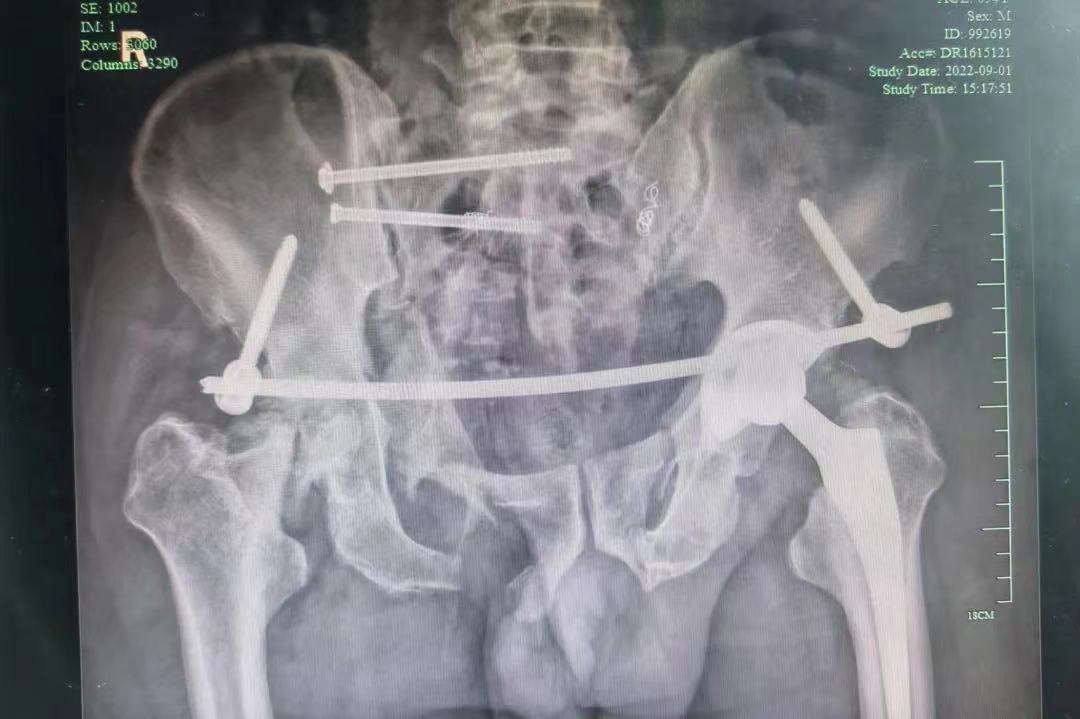

通讯员(于磊)近日,县人民医院急诊科、重症医学科(二)、介入科、骨科、肛肠外科、肝胆外科等多学科协作,成功救治一例严重骨盆骨折及腹腔脏器破裂等危重多发伤患者。 8月20日5时许,新昌县120急救中心接到交警电话,王家园一..